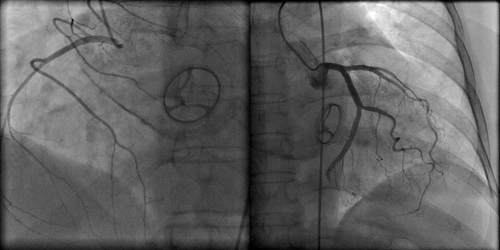

When a valve becomes so diseased that it impedes the delivery of blood to the body, open-heart surgery to replace the valve with a new one generally is recommended. Surgeons have noted in recent years a trend toward younger patients choosing biological valves, primarily because they do not want to deal with a lifetime of taking blood thinners and with the accompanying dietary restrictions and routine blood testing necessitated by a mechanical valve, Woo said.To compare the long-term risks and benefits of mechanical versus biological heart valves, the study, published in The New England Journal of Medicine, examined rates of mortality, stroke, bleeding and reoperation in patients who underwent heart-valve surgery at 142 hospitals in California between 1996 and 2013.

Patient records were obtained from the California Office of Statewide Health Planning and Development databases.Researchers examined the records of 9,942 patients who underwent aortic-valve replacement and 15,503 patients who underwent mitral-valve replacement during the study period.The aortic valve and the mitral valve are the most commonly replaced heart valves."Our research likely contains the largest number of patients ever studied to examine this issue," Woo said.The study showed that for patients undergoing mitral valve replacement, a mechanical valve is actually beneficial until the age of 70. On the other hand, for patients undergoing aortic valve replacement, the benefit of implanting mechanical valves ceased after the age of 55, the study said.